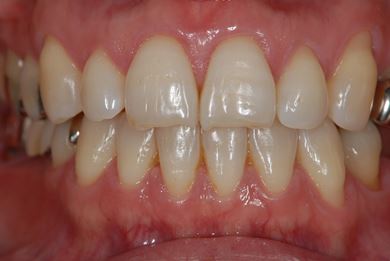

| 主訴 | ブリッジの支えとなっている歯が虫歯になり、ブリッジが難しくなったため、インプラントか義歯かの相談で来院。 | ||||||||||||||||||||||||||||||||

| 治療方針 | 抜歯と同時にインプラント治療を行い、治療期間を短縮する。 | ||||||||||||||||||||||||||||||||

| 治療内容 | インプラント4本(抜歯即日スピードインプラント治療)、ハイブリッドセラミッククラウン6本 | ||||||||||||||||||||||||||||||||

| 総治療費 | 1,236,165円 | ||||||||||||||||||||||||||||||||

| 治療期間 | 1年5ヶ月 |